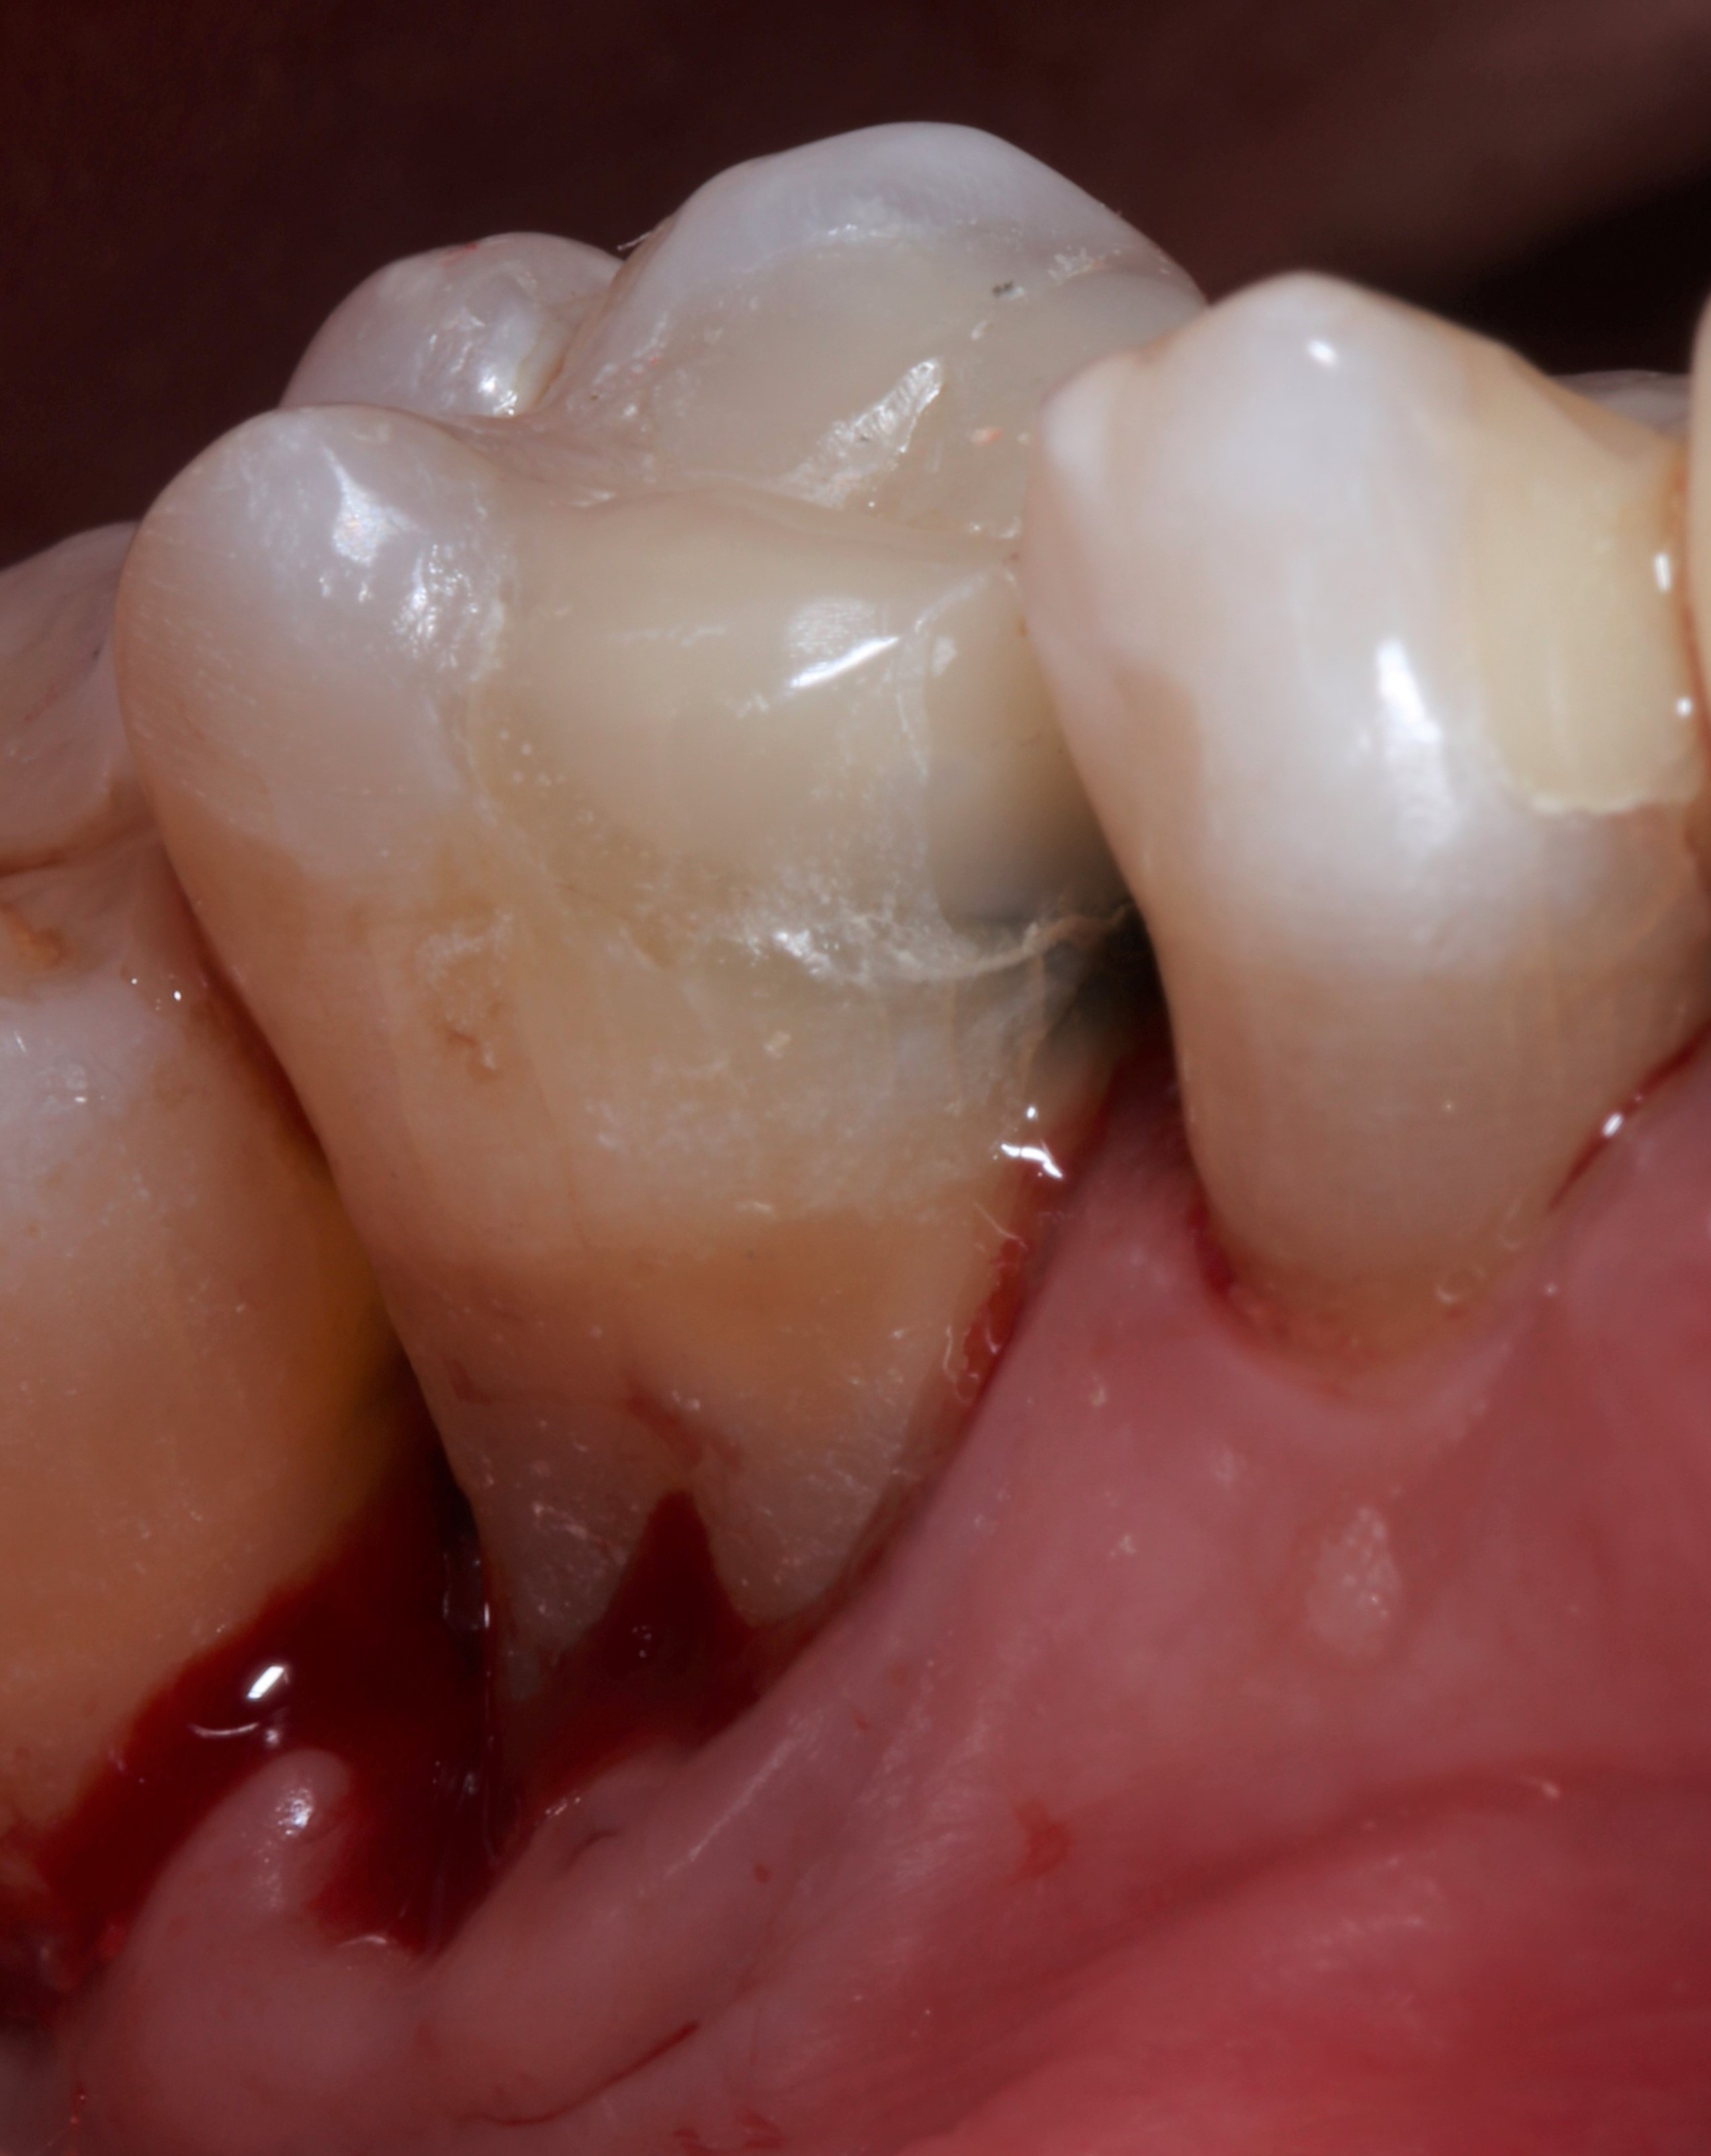

2. Ακτινογραφική εικόνα της απώλειας οστού γύρω από τις ρίζες δοντιού λόγω περιοδοντίτιδας.